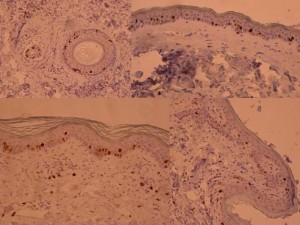

ki-67 staining of reticulo-acanthotic type of SKs.

ki-67 staining of reticulo-acanthotic type of SKs.

ki-67 staining of reticulo-acanthotic type of SKs.

ki-67 staining of reticulo-acanthotic type of SKs.